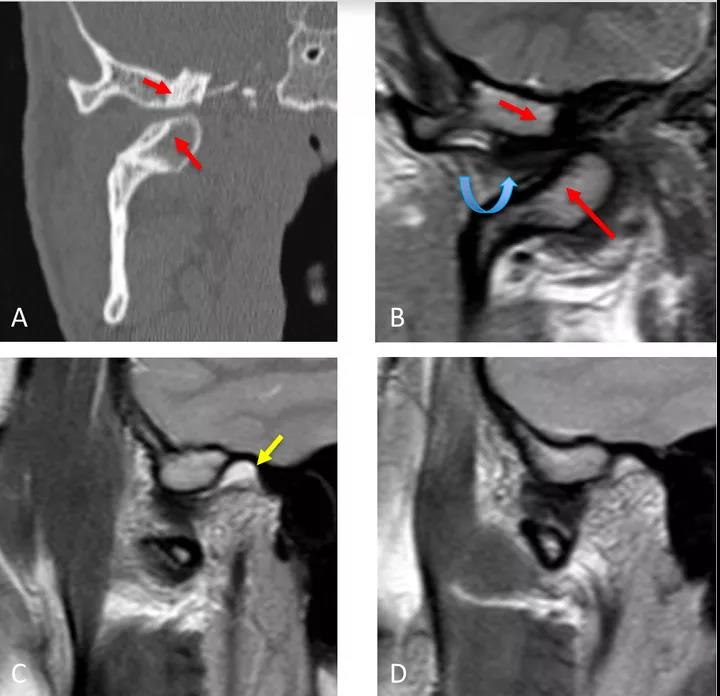

病例二:顳下頜關節(jié)脫位

冠狀面CT圖(A)和冠狀面PDWI圖(閉口)(B):顯示由于先前骨折導致的下頜髁突內側移位的顳下頜關節(jié)脫位,與骨折畸形愈合、前上髁和后顳嵴硬化(紅色箭頭)相關。關節(jié)盤位于下頜骨髁突和顳突之間,失去正常的形態(tài)(彎曲箭頭)。

矢狀位T2WI圖(閉口)(C):顯示正常位置的下頜骨髁突及關節(jié)積液(黃色箭頭)。

矢狀位PDWI圖(開口)(D)顯示髁突明顯偏移。